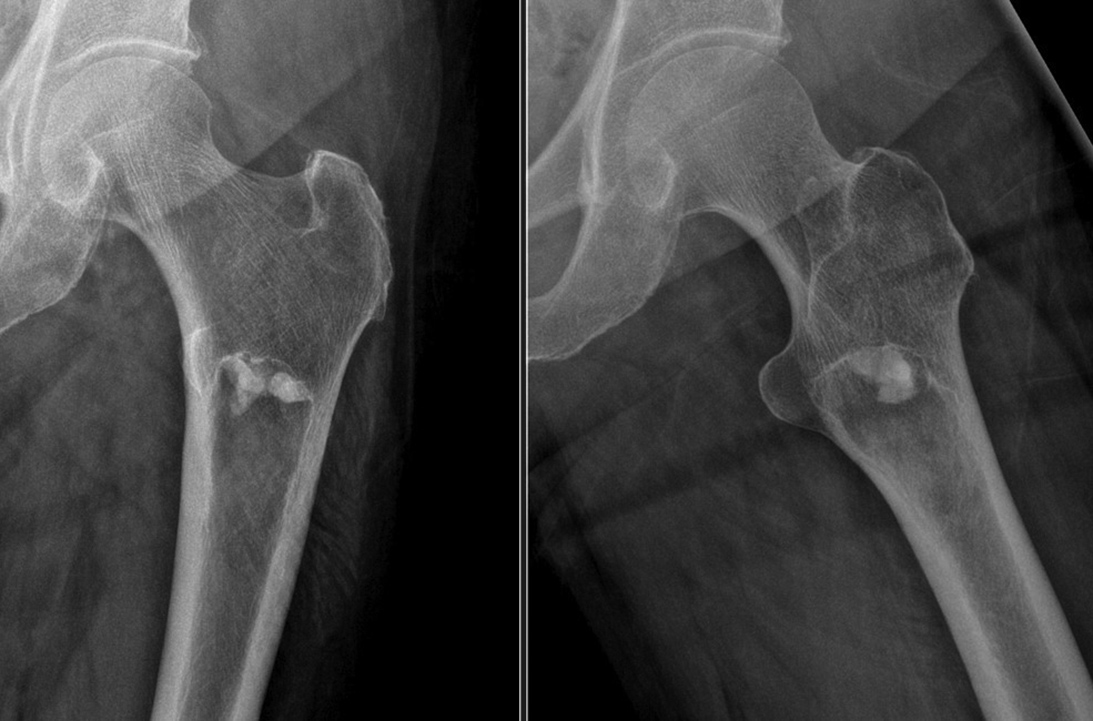

Bone-RADS is a novel scoring system to differentiate lytic bone lesions

Orthopaedic surgeons often encounter radiographic findings that raise concern for undiagnosed malignancies, with diagnoses ranging from benign bone cysts to metastases or primary bone tumors.